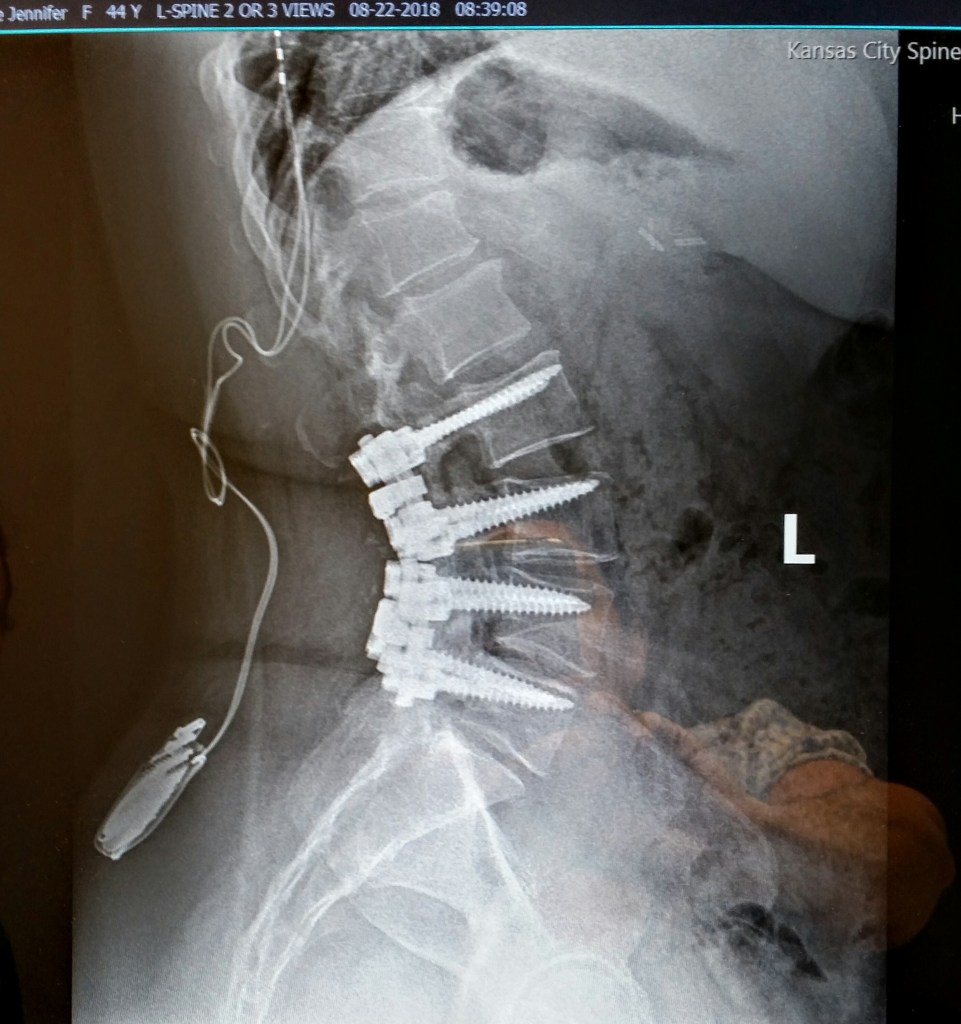

Hi everyone. First of all, sorry about the lack of post last week. I was scheduled for surgery on Monday morning and I planned to apologize when I came back, but my surgery has been rescheduled for May 29th. So it looks like I have more I need to do before then. If you aren’t familiar with my struggle, click here to read more: https://jenniferhaskin.com/2020/03/16/the-opioid-epidemic/ (the pictures maybe graphic to some)